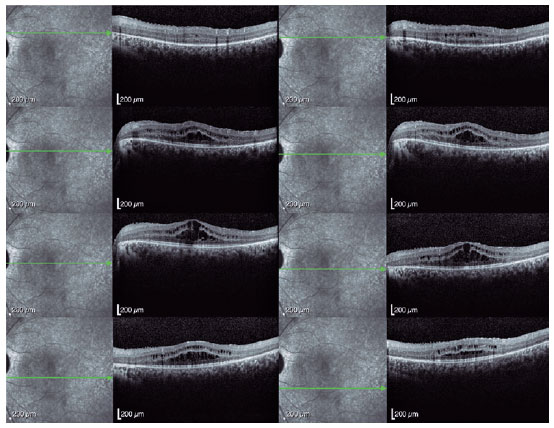

Spectral-domain optical coherence tomography (Spectralis, Heidelberg Engineering GmbH, Heidelberg, Germany) revealed a bilateral cystoid macular edema that was most prominent in the left eye (Figures 3 and 4). Genetic screening revealed heterozygous variants in the CRB1 gene (c.2843G>A and c.2506C>A), confirming the diagnosis of RP. The patient´s intraocular pressure (IOP) remained high, despite maximum medical treatment and the angle remained closed despite YAG laser iridotomy. Trabeculectomy was performed in the left eye to achieve adequate IOP control.

03-fig03.jpg)